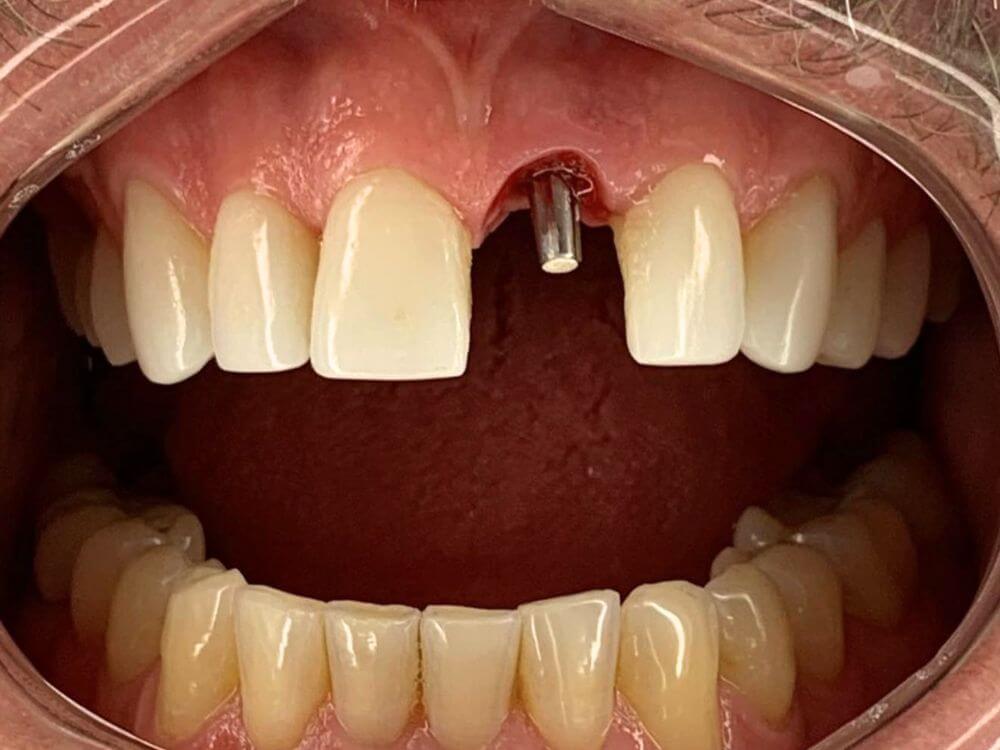

A melhor solução para quem perdeu um único dentes. Procedimento simples e rápido. Muito utilizado em casos de fraturas dentárias e tratamentos estéticos.